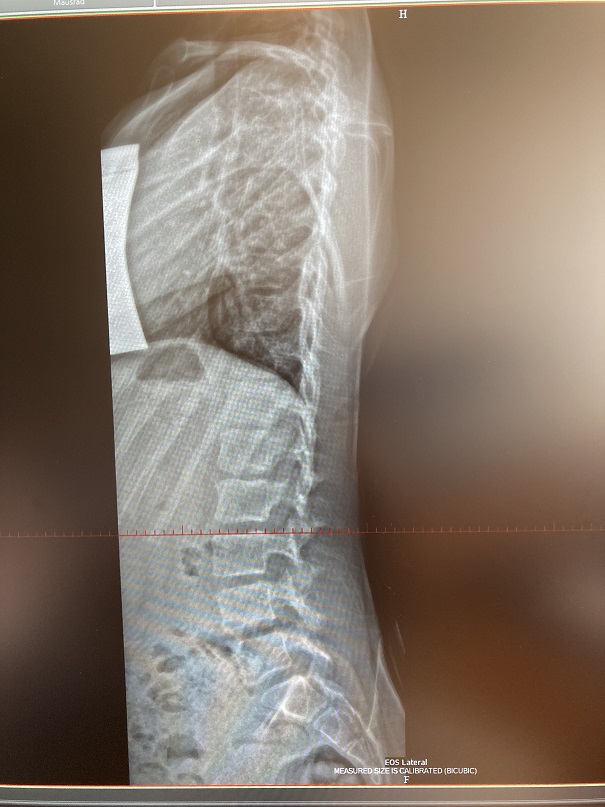

MRT Bild habe ich an Rahmouni zugeschickt und die Begründung von Herrn Harzer war - "eine leichte Überkorrektur". Der Arzt meine, meine Tochter sollte kein Korsett mehr tragen und beobachten, bis alles wieder zurück kommt und wenn nicht, dann braucht sie ganz anderes Korsett. Zu warten war mit viel zu gefährlich. Ich war sehr frustriert und bin nach Bad Sobernheim gefahren, um noch eine Meinung zu hören. Dort haben wir das neue Röbild gemacht. Alles hat sich bestätigt - meine Tochter hat jetzt drei Bögen anstatt zwei - die alten Krümmungen von Gradzahl fast unverändert. Dazu noch Flachrücken...

IMG_E0124 Paint.jpg

(145.23 KiB) Noch nie heruntergeladen

Flachrücken paint.jpg

(131.67 KiB) Noch nie heruntergeladen